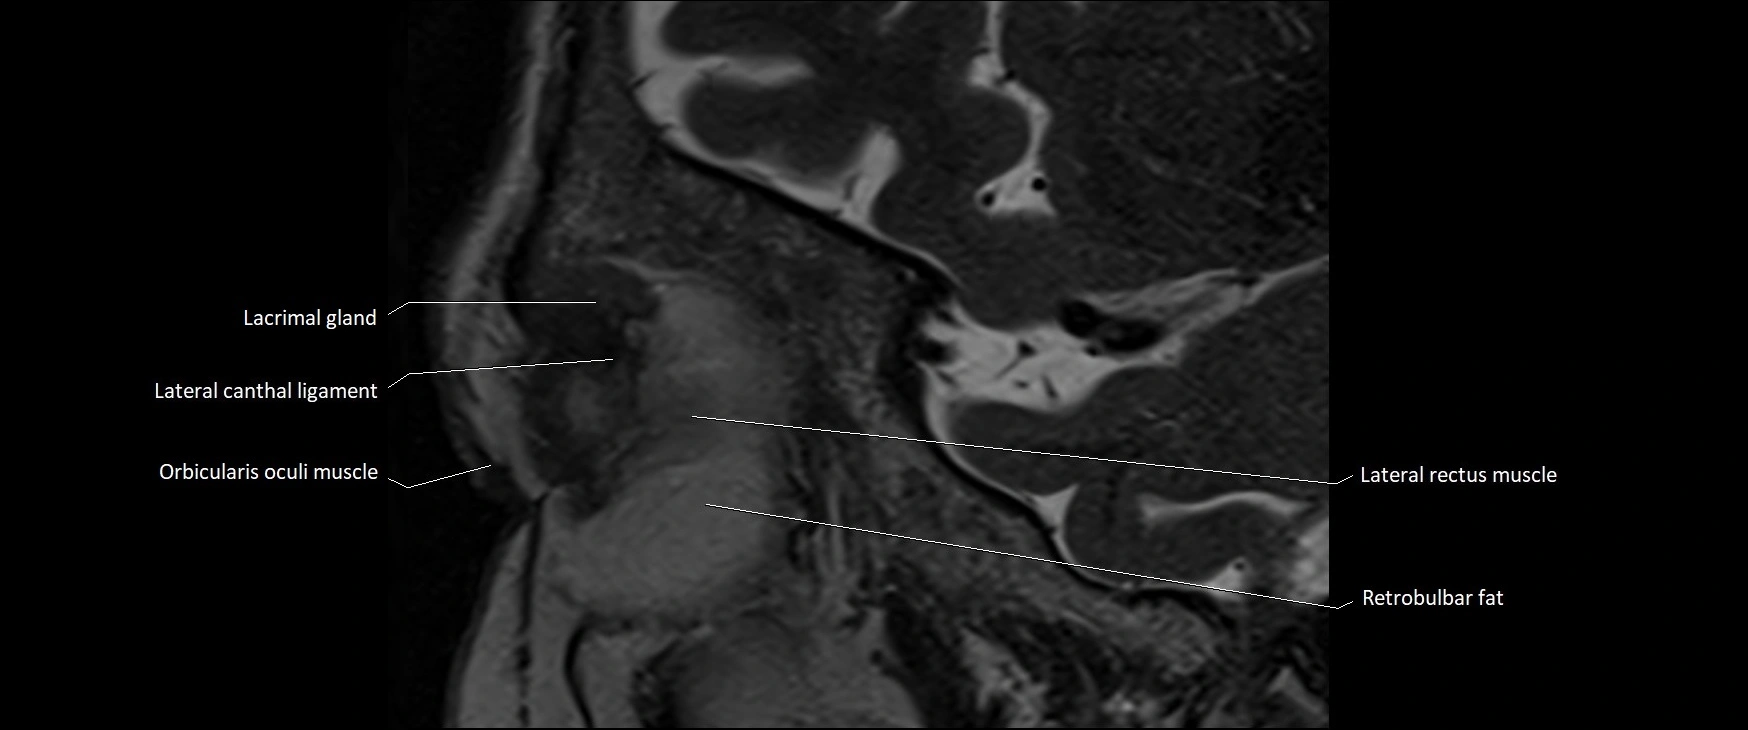

MRI images